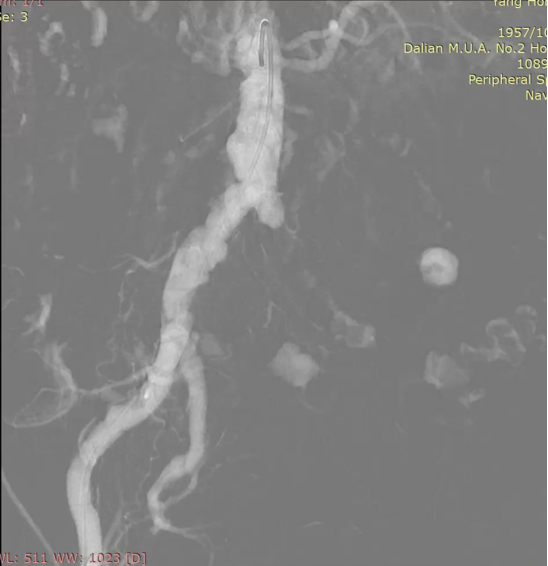

图为:穿刺后,导丝上行阻力,软针造影,髂动脉 极细

图为:腹主动脉造影,左髂动脉主干 不易 分辨

图为:0.018导丝配合pig导管+CXI支持导管翻山,真腔通过

图为:于左髂动脉分叉处依次置入cordis(10-8)接ev3(8-120)支架各1枚,球囊 轻度 后扩

图为:股浅动脉 待二期处理